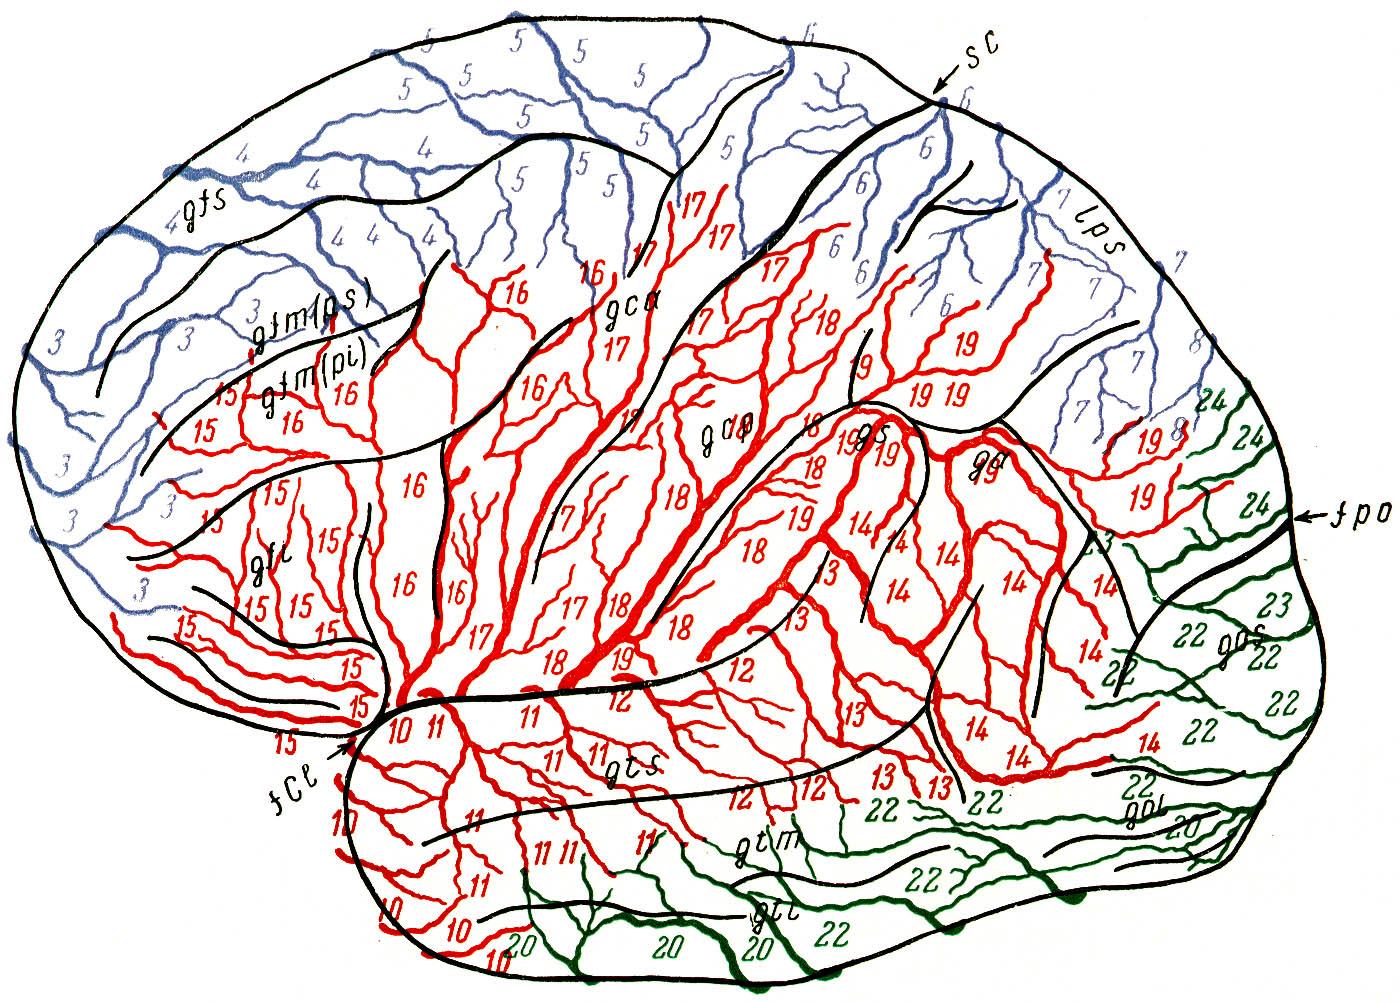

Схема чувствительных зон новой коры мозга